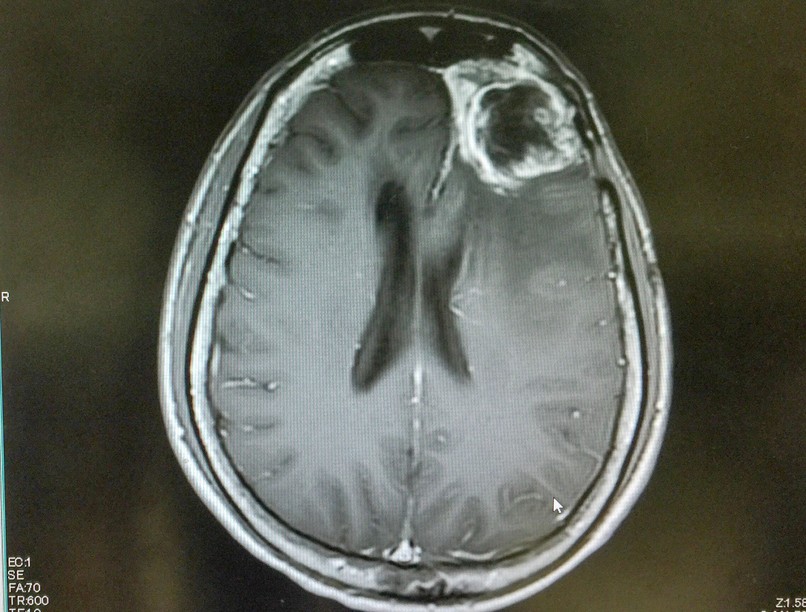

Kínai és Egyesült Államokbeli tudósok működtek együtt egy új, növényi alapú nanorészecskés kezelés kifejlesztésében a glioblasztóma, a leghalálosabb agyrák kezelésére. Ezeket a bardoxolon-metil (BM) nevű fitokemikáliából készített nanorészecskéket úgy tervezték, hogy áthatoljanak a vér-agy gáton, és közvetlenül a daganatsejteket célozzák meg. A kutatás a Small Science című tudományos lapban jelent meg.

Az agydaganatok az érintett agyi terület nyomásával vagy károsításával az agyműködés zavarát okozhatják. A glioblasztóma jelenlegi kezelési protokollja a daganat sebészeti eltávolításával kezdődik, majd sugár- és kemoterápia következik. Azonban a kezelés ellenére a daganat gyakran ellenállóvá válik, ami korlátozza a terápia hatékonyságát.